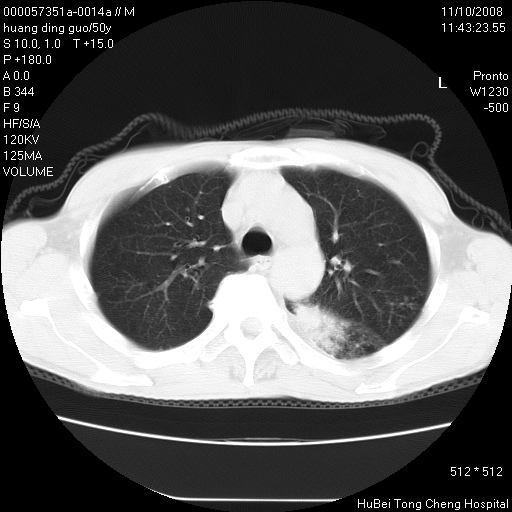

患者 男,50岁。左侧腰背部疼痛3月余,伴消瘦。平素健康,无传染病史。

胸部ct轴位平扫(层厚10mm,螺距1.5,重建间隔10mm),图像如下:

左肺下叶背段有一厚壁空洞,外壁呈锯齿状伴毛刺改变。空洞相邻胸膜有牵拉改变。左肺下叶血管支气管束不规则增粗,小叶间隔增厚。胸椎骨质破坏。考虑左肺下叶周围型肺癌伴左肺下叶癌性淋巴管炎、胸椎转移。

左肺下叶背段有一厚壁空洞,外壁呈锯齿状伴毛刺改变。空洞相邻胸膜有牵拉改变。左肺下叶血管支气管束不规则增粗,小叶间隔增厚。胸椎骨质破坏。考虑左肺下叶周围型肺癌伴阻塞性肺炎、胸椎转移。其他待排

左肺下叶背段有一厚壁空洞,内壁不规则,外壁呈锯齿状伴毛刺改变。空洞相邻胸膜有牵拉改变。周围呈絮状炎性改变,左肺下叶血管支气管束不规则增粗,小叶间隔增厚。胸椎骨质破坏。考虑左肺下叶周围型肺癌伴左肺下叶阻塞性肺炎、胸椎转移。